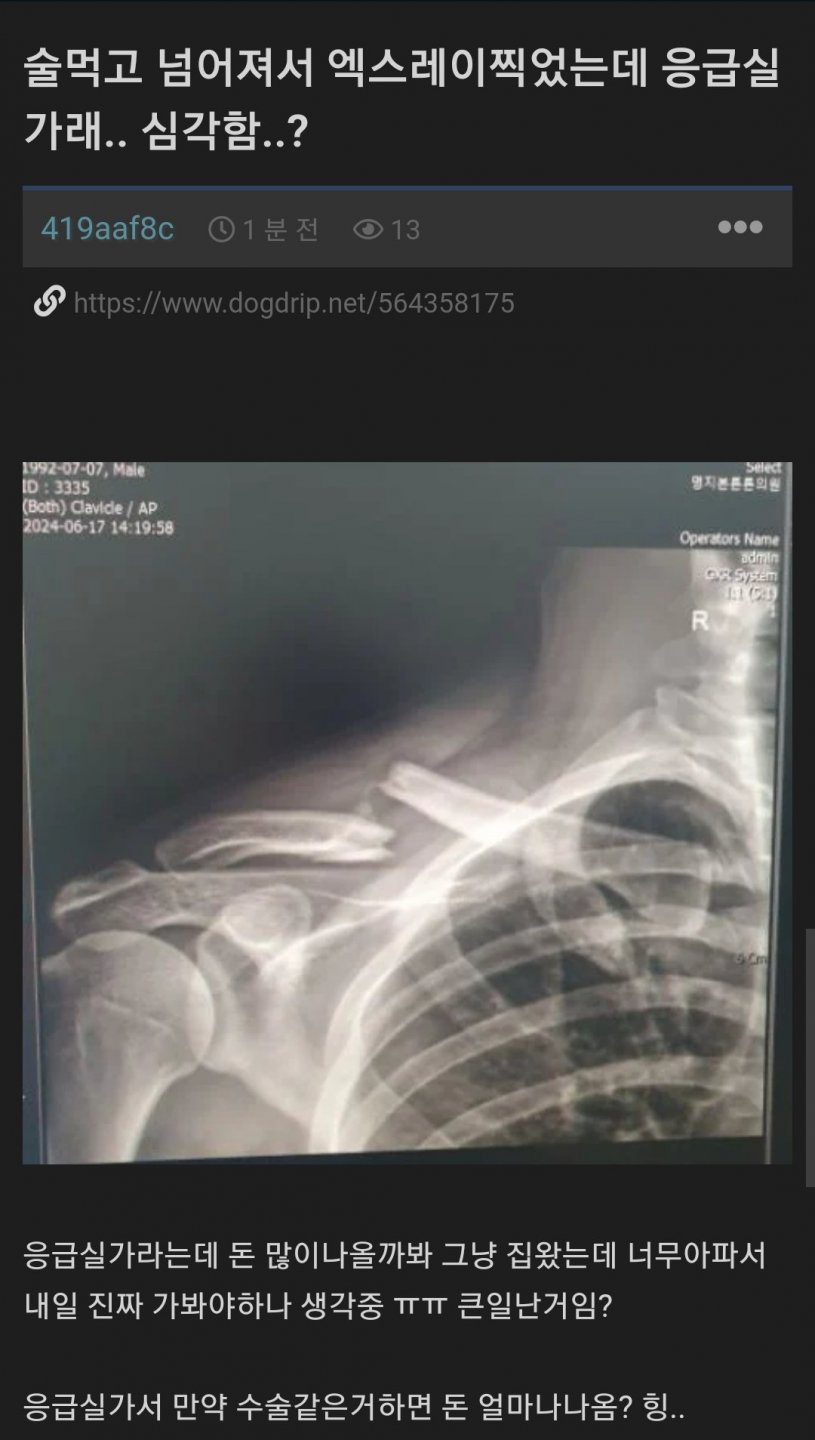

¼ú ¸Ô°í ³Ñ¾îÁ®¼ ¿¢½º·¹ÀÌ Âï¾ú´Âµ¥ ÀÀ±Þ½Ç°¡·¡

¼â°ñ°£ºÎ°ñÀýÀεð ¿ÜºÎ·Î Æ¢³ª¿Â°Å¹È Â÷¶ó¸® ´ÙÇàÀÌÁö ¾ÈÀ¸·Î ¹ÚÇûÀ½ Ŭ³ªµû

¾Æ´Ñ°¡ °ß¼â°üÀý Àۻ쳰ǰ¨..,

±Ùµ¥ ³Ñ¾îÁ®¼ ÀýÄÉ µÉ Á¤µµ¸é ¾îÄÉ ³Ñ¾îÁ®¾ßÇϳª¿©

±º´ë¿¡¼ ÀÌ·¸°Ô ºÎ·¯Á³¾ú´Âµ¥ ¾ö»ìÀ̶ó°í º´¿ø ¾Èº¸³»ÁÖ°í ÇØ¼ ¾ÆÁ÷µµ ¿ÞÂÊ¿¡ ÈûÀÌ Àß ¾Èµé¾î°¡ ¤Ð

¹ÌÄ£³ðÀΰ¡ ¾îÄÉ Âü¾Æ??